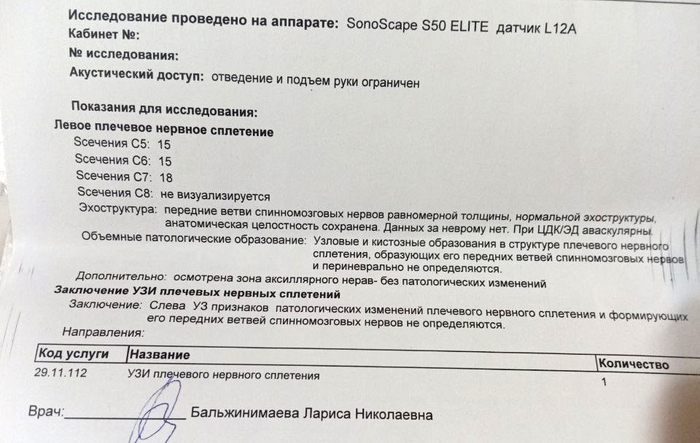

Врач-нейрохирург, специализирующийся на подобных случаях, пересмотрел полученные изыскания и проверил работоспособность конечности. Вердикт был суров - ситуация тяжёлая, но поправимая. Вся рука функционирует отлично, даже с учётом двух месяцев в повязке. Сустав в плече работает плохо, потому что разрабатывать его не даёт боль, но лучше починить старое, чем потом привинчивать новое. Пилюльки для снятия нейропатической боли прописаны правильные, но дозировку нужно больше раза в два. Плюс добавить антидепрессанты, которые так же работают со снятием боли, пусть даже будут жёсткие побочные эффекты. И быстренько разрабатывать руку, как только боль немного спадёт. Разработаю руку - победю. Пожалею себя - будут плохие последствия.

Диагноз невропатолога Комплексный регионарный болевой синдром подтверждён. Руку не отрезаем, нервы не трогаем, посттравматическая нейропатия лучевого нерва под вопросом.